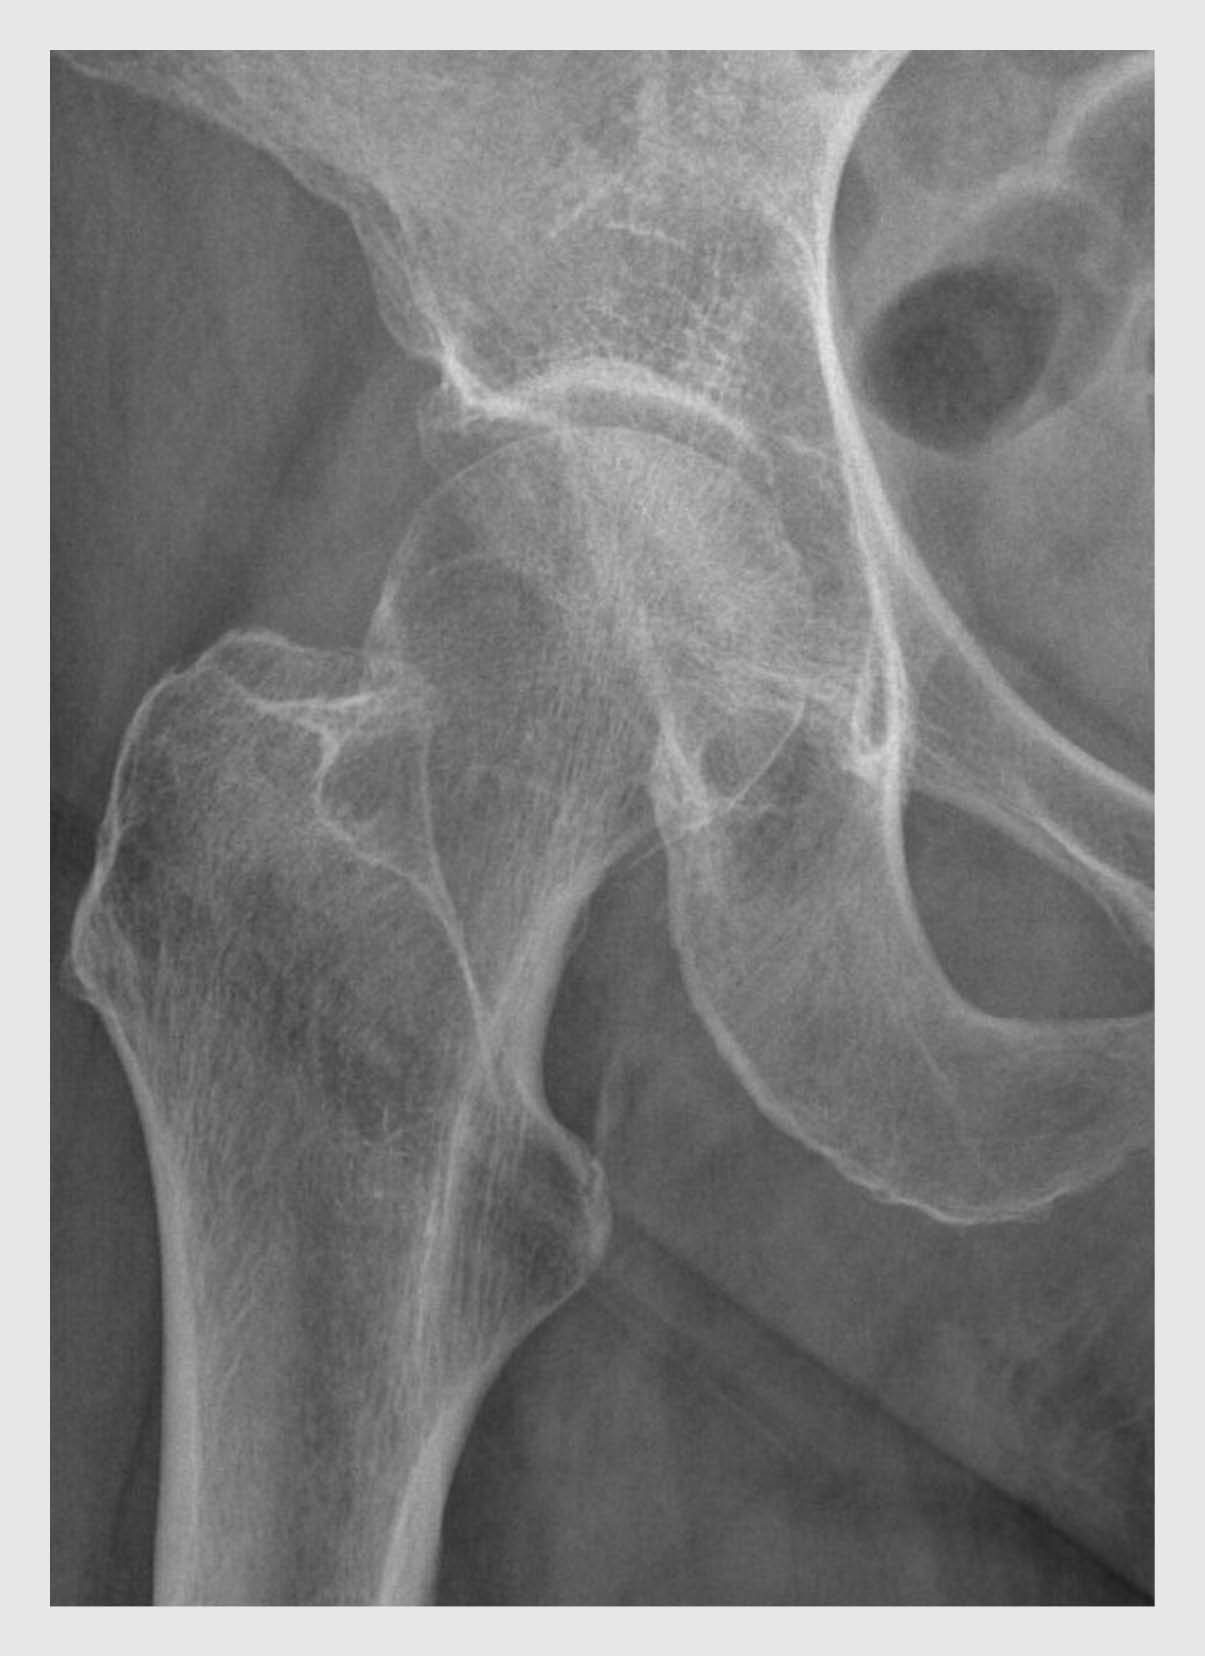

Figuur 1

Röntgenfoto van de heup van patiënt A

Figuur 1 | Röntgenfoto van de heup van patiënt A

Een conventionele röntgenfoto van de rechter heup van een 74-jarige vrouw na een val in huis. Er zijn geen fracturen van het proximale femur of van het os pubis zichtbaar. De femurhals is echter lastig te beoordelen doordat het trochanter major deels over de femurhals projecteert. Dit komt in de praktijk vaker voor en leidt tot een lagere sensitiviteit van een conventionele röntgenfoto bij collumfracturen.